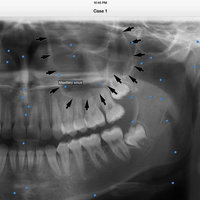

iPanoramic

Panoramic radiographs provide a quick overview of the patient’s teeth, jaws, and bone. This is useful for diagnoses and treatment planning.

The app provides dental students and dental hygiene an easy and fun way to master different anatomical landmarks. Dental practitioners can use the app to refresh their knowledge about panoramic radiographs. The app can be used a quick reference when needed. It's fully interactive and allows knowledge assessment through a quiz mode.